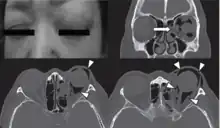

| Woman with preorbital swelling in orbital emphysema shown in CT scans | |

The signs and symptoms of orbital emphysema vary depending on the original cause, but it is preliminary associated with swelling, bruising, and tenderness around the impacted eye.[29] It may also involve proptosis or the deterioration of vision, typically diplopia.[1][23] The entrapped air may cause an acute increase in the intraocular pressure or vascular compromise that restrict ocular motility, prohibit the closure of eyelids, and the loss of sensation over the upper cheek areas.[30]

Physical examination

Physical examination of the eyelid can be done by the palpation for the pathognomonic cracking, crepitation,[11] and tense tissue[35] on the upper and lower eyelids. The findings of the examination are supported with the medical history of the patient and confirmed with orbital CT.[6]

Computed tomography (CT)

Computed tomography is effective and sensitive in the diagnosis of orbital emphysema,[3][37] as it can confirm the anatomical location and size of air, bony defects, indentation of the eyeball, and the condition of the optic nerve, as well as the presence of any extraocular muscle entrapment and herniation of preorbital fat into the sinus cavities.[3][15][38] The location of the orbital emphysema is present near the site of the fracture.[1][3] The scans are usually taken along the transverse plane. Transverse images allow the evaluation of fractures in medial and lateral orbital walls. By reformatting these transverse images or taking coronal images, the examination of orbital floor and roof is permitted. Helical scanning is preferred as it has a lower imaging time and radiation dose comparing to conventional scanning, especially when reforming transverse helical scans into coronal images.[3] The staging of orbital emphysema can then be determined with visual acuity examination and ophthalmoscopy.[6] A disadvantage of using a CT scan is that when detecting air after orbital trauma, the presence of a wooden foreign object can give a false positive result of orbital emphysema. The wooden object can mimic the presence of orbital emphysema. Therefore, patients’ medical history is crucial in making the correct diagnosis.[3]